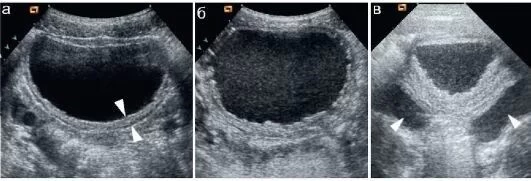

Ультразвуковое обследование мочевого пузыря дает возможность врачу визуализировать структуры выводящей системы неинвазивным способом. Работа УЗИ основана на различном отражении невидимой звуковой волны от тканей и образований различной плотности, что показывает строение данного органа с наличием:

- изменений в толщине стенки;

- нарушений контура, отечности, слоистости стенки;

- наличия пристеночных объемных образований, взвеси в моче;